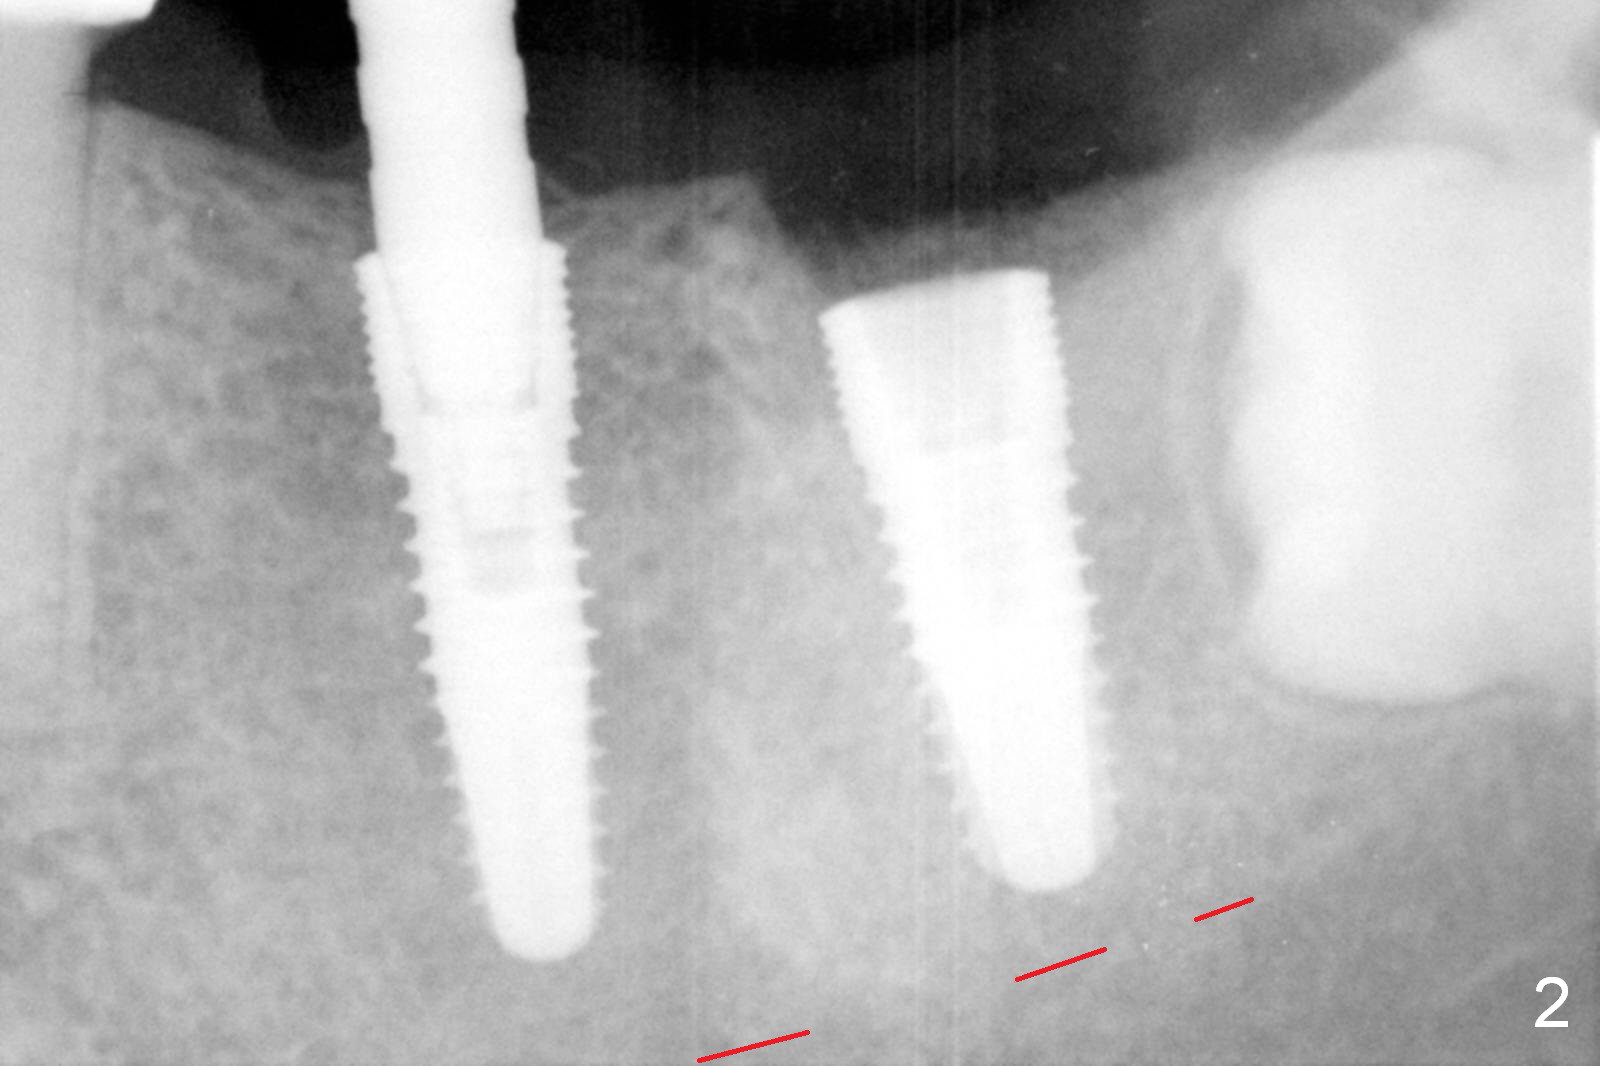

Infiltration anesthesia is enough for initial osteotomy at the site of #19 (Fig.1), but not for sectioning the tooth #18. Block anesthesia has to be administered. Fortunately it is safe to start osteotomy at #18 (~ 3 mm beyond the socket bottom, Fig.1 (red dashed line: the superior border of the Inferior Alveolar Canal (IAC))). A 4.5x14 mm implant is stable at #19, while a 5x12 mm one at #18 is not (Fig.2). Unfortunately bone graft has been placed. When the implant is removed, a 4.5x14 mm drill is used to deepen the osteotomy for 2 mm. The patient reports mild discomfort later on. Hemorrhage occurs, which is stopped when the same implant is re-placed. There is no stability. The implant is removed (Fig.3,4). More bone graft is placed, followed by collagen plug. It appears that bone graft has been pushed into the IAC (Fig.4 arrowheads). Medro dose pak is prescribed. In fact, no paresthesia is reported postop.